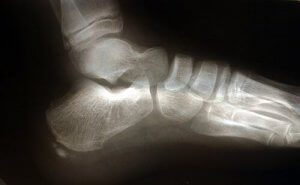

प्लांटर फेशियाइटिस पैर के तलवे में प्लांटर फेशिया की सूजन है। प्लांटर फेशिया एक लिगामेंट जो एड़ी की हड्डी को प्रॉक्सिमल फैलेंजेज से जोड़ती है और हर स्टेप के साथ रबर बैंड की तरह फैलती और सिकुड़ती है।

भारी प्रेशर और प्रतिरोध झेलने के कारण प्लांटर फेशिया (plantar fascia) एक बहुत व्यापक, मोटी टिशू है। इस लिगामेंट में सूजन होने से एड़ी में दर्द होता है। यह इस अंग में दर्द की सबसे अहम वजह है।

पैर की एनाटोमी

कई संरचनाएं हैं जो प्लांटर फेशिया को ओवरलोड करने में भूमिका निभाती हैं। अकिलीज़ टेंडन वह लिगामेंट है जो गैस्ट्रोनेमियस मसल्स यानी काफ और सोलियस मसल्स को एड़ी की हड्डी से जोड़ती है।

अकिलीज़ टेंडन के पीछे आने से एड़ी की हड्डी पर दबाव बढ़ जाता है, जिससे प्लांटर फेशियाइटिस पर भी दबाव बढ़ जाता है। इसका मतलब यह है कि आपके अकिलीज़ की स्ट्रेचिंग नहीं करने से फेशियाइटिस हो सकता है क्योंकि यह आपके पैर पर बहुत ज्यादा दबाव डालता है।

आपके शरीर की बनावट में ध्यान रखने वाली एक और बात फुट स्ट्राइक है। दूसरे शब्दों में इसका मतलब यह है की आपका पैर जमीन को कैसे छूता है। उदाहरण के लिए सपाट पैर वाले लोगों में प्लांटर फेशिया को ज्यादा खींचने का रुझान होता है। इससे इस टिशू पर ज्यादा दबाव पड़ने के कारण टूट-फूट का खतरा बढ़ जाता है।

प्लांटर फेशियाइटिस में अक्सर कोई अस्थि-स्कंध जुड़ा होता है, हालांकि यह एक निर्धारक कारण नहीं है। प्लांटर फेशियाइटिस को लम्बे समय तक छोड़कर रखने या ठीक तरीके से इलाज न कराने से व्यक्ति अपने चलने में बदलाव देख सकता है। नतीजतन इससे घुटनों, पीठ या गर्दन में तकलीफ हो सकती है।